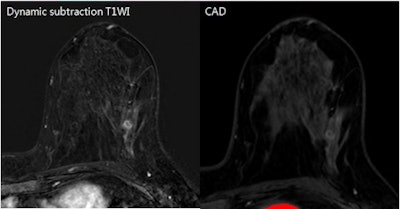

Despite its ability to improve the detection of breast cancer, breast MRI computer-aided detection (CAD) software still misses some. Several factors can affect the detection capabilities of the software, Korean researchers have found.

CAD systems for breast MRI provide pixel-by-pixel kinetic information of dynamic enhancement above a certain threshold level. While it's been known to improve specificity for breast cancer by better demonstrating the presence of enhancement and delayed-enhancement features, CAD still doesn't detect some cancer cases, Choi said.

The researchers applied CADstream breast MRI CAD software (Merge Healthcare) using a 50% threshold of initial enhancement. They then retrospectively reviewed the CAD results and noted the patient's age, histopathological factors (such as lesion size, pathological size, invasiveness, nuclear grade, and the presence of extensive intraductal components), and IHC factors.